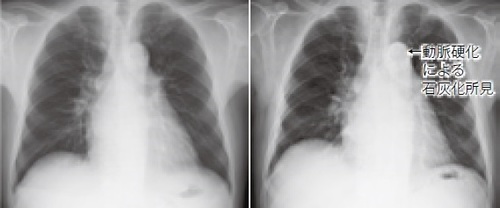

右:2003年3月(74歳)、左:2019年5月(90歳)

右:2009年3月(57歳)(大動脈弓部には石灰化がない)、左:2017年3月(65歳)(大動脈弓部に石灰化がある)。